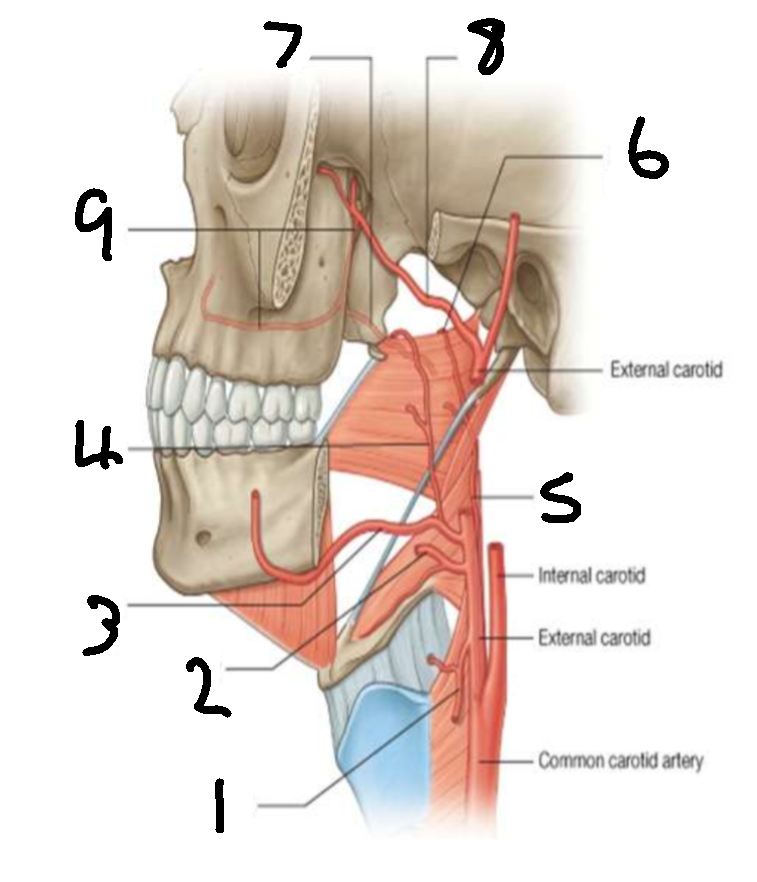

What is 1?

superior thyroid artery

What is 2?

lingual artery

What is 3?

facial artery

What is 4?

ascending palatine artery

What is 5?

ascending pharyngeal artery

What is 6?

palatine branch of pharyngeal artery

What is 7?

lesser palatine artery

What is 8?

maxillary artery

What is 9?

greater palatine artery